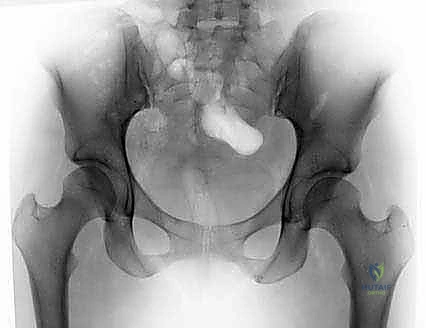

- الأشعة السينية الرقمية (X-rays): لتقييم البنية العظمية، زوايا الحُق، وتحديد وجود نتوءات الكامة أو الكماشة، واستبعاد الخشونة المتقدمة.